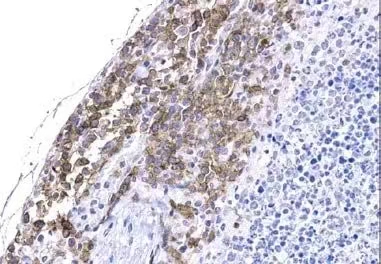

全球首款IHC-P验证抗体: Witlow/218 Linker(F2G3S)Rabbit mAb #47414

直接在FFPE实体瘤切片中定位CAR细胞,避免RNA原位杂交的假阳性风险

IHC-P:适用#47414对NSG小鼠脾脏中经异种移植的Raji B细胞淋巴瘤进行免疫组织化学分析,该小鼠脾脏中灌注了靶向CD19的原代人类CAR-T细胞